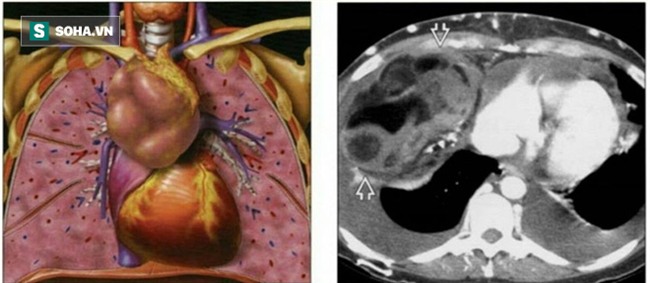

Phát hiện khối u chiếm toàn bộ khoang lồng ngực trái, kéo dài từ nền cổ tới gần sát cơ hoành, đè đẩy tim và các mạch máu lớn, mật độ chắc, phát triển lan tỏa ra xung quanh vào khoang màng phổi 2 bên, chèn ép đẩy lệch khí quản, tim , phổi và mạch máu, u bọc quanh các dây thần kinh.

ThS.BS Hựu cho biết: "U tế bào mầm thường xuất phát từ mô tuyến sinh dục. Những trường hợp ngoài tuyến sinh dục thì vị trí phổ biến nhất là ở trung thất trước của lồng ngực. Khối u phát triển lan tỏa chèn ép, xâm lấn và các cơ quan lân cận: phổi, màng tim, khí quản, mạch máu lớn trong ngực…".